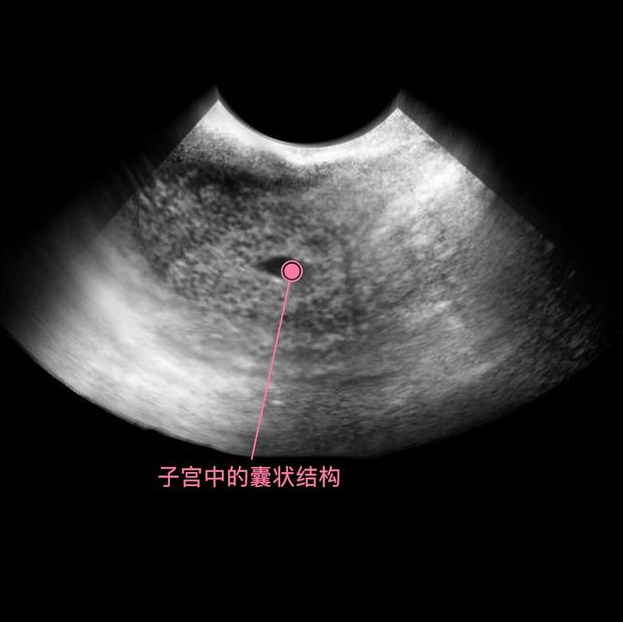

上图可见子宫中的囊状结构,胎儿由两层的组织构成胚胎,所有的器官和组织都是有这些组织发育而成,胚胎羊膜囊的空腔中,开始有羊水积聚,为将来包裹和保护胎儿做准备。